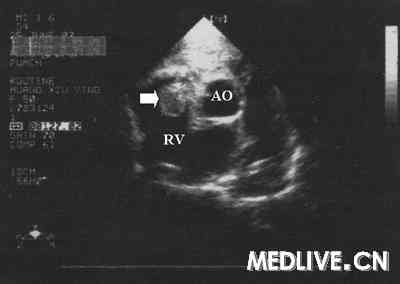

UCG示右室内肿块

图3  UCG示右室内肿块(↑)。RV=右室,AO=主动脉